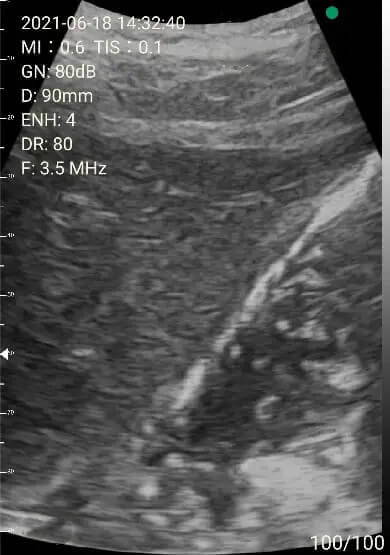

Case 2: Pleural effusion

Demonstration of bilateral pleural effusion. The left picture shows a small amount of pleural effusion with collapsed lung, diaphragm and spleen. The right picture shows a large amount of pleural effusion, diaphragm and liver.

These images were obtained from an 80-year-old man with heart failure and general edema. Chest film showed bilateral blunt costophrenic angles. We planned to place a pigtail to drain his pleural effusion out.